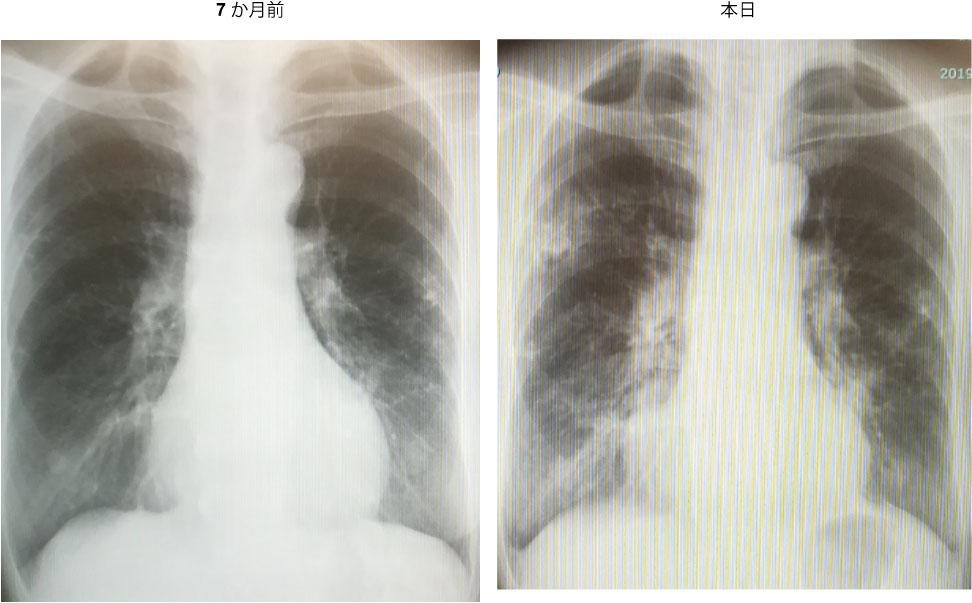

@69ΞB«B14NOAMACΗΖff³κAθϊΚ@B7ϊO©η38δΜMA’Puͺ±BπϊA\αͺo»BπMάΘΗΜpΝ³΅B

@ΉXpFMACΗ«AΌ€ΚΉ